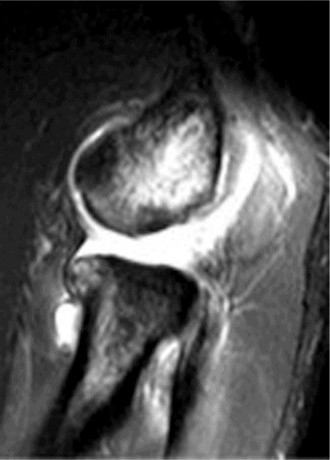

The correct answer is (B). An MRI showing a rotator cuff tear is considered diagnostic of a rotator cuff tear because of its high sensitivity, specificity, and accuracy. It has superb soft tissue imaging abilities (see Fig. 2–5). However, it should be noted that while MRI usually can differentiate between partial- and full-thickness rotator cuff tears, this varies with the power and accuracy of the MRI facility. This is also true with the ability of MRI to differentiate between partial-thickness rotator cuff tears and subacromial bursitis. An arthroscopy is needed for definitive differentiation of these pathologies.

Figure 2–5_Coronal oblique view MRI slice of a left shoulder. (Reproduced with permission from Smithius R and van de Woude HJ. Shoulder MR Anatomy: Normal Anatomy, Variants, and Checklist. _Radiology Assistant. April 2, 2012.)

MRI remains the most popular imaging modality for diagnosing rotator cuff tears. Normal rotator cuff tendon appears dark on both T1 and T2 sequences. Tears may be noted as being full-thickness, articular-sided, bursal-sided, or intrasubstance. They are visualized as a disruption in the regular contour of the tendon and increased signal intensity on T2 sequences. Occasionally, an MR arthrogram may provide additional information regarding a cuff tear, although this is not routinely ordered.

The correct answer is (D). T2 sequence causes most soft tissues, including muscle and tendon, to appear dark and inflammation, such as at the site of a tear, to appear bright. This means that if there is a rotator cuff tear, there will be a bright spot along the course of the dark rotator cuff tendon. This is easiest to pick out in the coronal plane because the tendon runs in this plane, allowing one to view the entire supraspinatus tendon and tear in one cut.